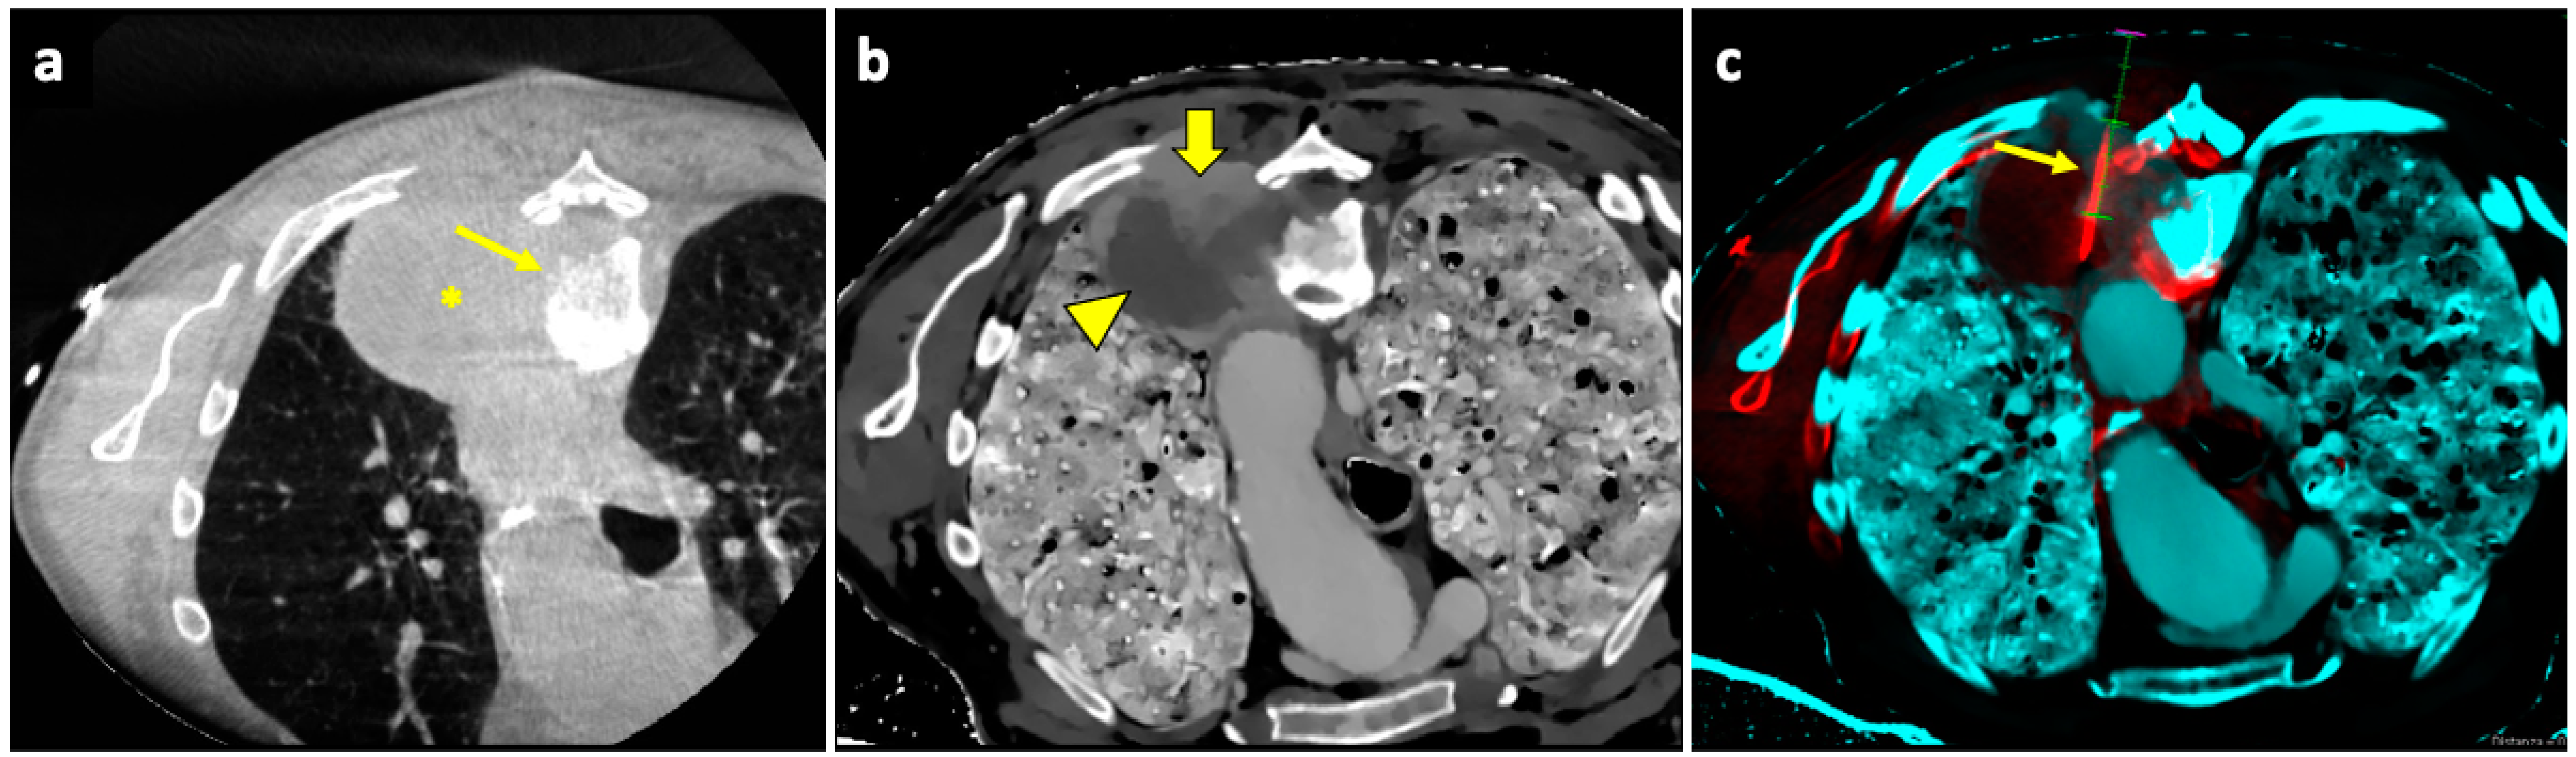

A useful technique in this setting is fusion imaging, which is defined as the process of overlapping imaging datasets from different modalities into a single composite imaging dataset. By using dedicated software, it is possible to overlap pre-procedural 18F-FDG PET/CT images to intra-procedural CBCT images, thus integrating functional and anatomical data, and to guide the needle towards the viable and metabolically active portion of the target lesion. An example of a biopsy guided by fusion imaging between CBCT and PET-CT is illustrated in Figure 5.

Figure 5.

Biopsy guided by fusion imaging between CBCT and 18F-FDG PET-CT. (a) Preprocedural PET-CT showing a large mass in the upper lobe of the left lung, with a metabolically active peripheral area (arrowhead) and a central photopenic area (asterisk). (b) Coronal fused image obtained by overlapping the intraprocedural unenhanced CBCT volume to the preprocedural PET-CT volume; note that the mass has no distinguishable components on the CBCT images. Fusion imaging allows us to identify the metabolically active portions (arrowhead) and to place the target point (thick arrow) within this area. (c) The procedural PET-CT volumetric data and the virtual trajectory are displayed over the real-time fluoroscopic images as guidance during the biopsy. (d) Axial fused image obtained by overlapping the intraprocedural CBCT to the preprocedural PET-CT images shows that the biopsy needle (thin arrow) is in the right direction, i.e., towards the most metabolically active part of the mass (arrowhead). Histology revealed pulmonary adenocarcinoma.

It has been demonstrated that the technique is effective [133], increasing the chances of obtaining diagnostic samples while performing fewer biopsies, improving the quality of histological analysis [134].

An example of a biopsy guided by fusion imaging between pre-procedural spectral CT and intra-procedural CBCT is illustrated in Figure 6.

Figure 6.

Biopsy guided by fusion imaging between CBCT and 18F-FDG PET-CT. (a) Axial intraprocedural CBCT image with the patient in prone position reveals a large lung lesion (asterisk) in the apical segment of the left lower lobe, causing erosion of the adjacent vertebral body (thin arrow); no significant difference in cellularity within the lesion can be appreciated in the unenhanced CBCT. (b) Axial CT image reconstructed with spectral Z-effective grayscale map demonstrates significant tissue differentiation within the lesion, allowing for identification of a portion with high cellularity (thick arrow) and another component with low cellularity and high fibrous tissue content (arrowhead). (c) Intraprocedural fusion image of CBCT and Z-effective images with the needle inserted in the cellular portion (thin arrow). Abbreviations—CBCT: cone-beam-computed tomography; CT: computed tomography.